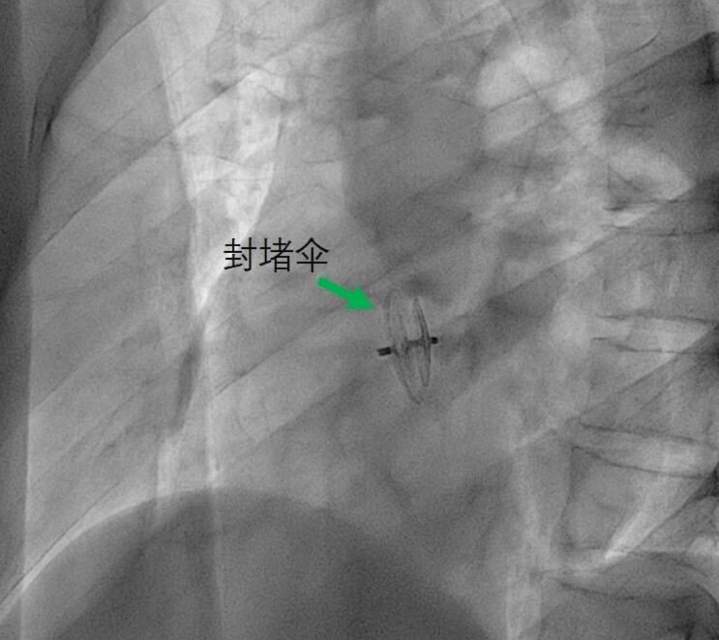

经导管封堵PFO预防PFO相关卒中。

术后局部压迫4-6小时,常规肝素抗凝48小时。口服阿司匹林100mg+氯吡格雷50-75mg,6个月。6月内所有侵入性操作或手术,则预防感染性心内膜炎。6月后,口服阿司匹林100mg至1年。